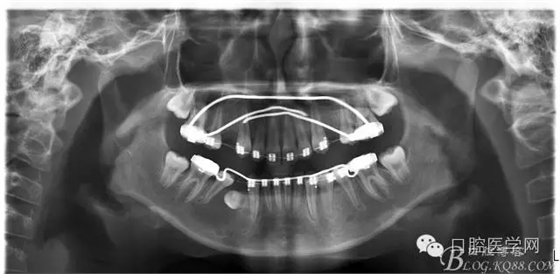

設(shè)計:

1:SWA.

2:拔牙矯治,拔出4顆第一前磨牙。

3:上下頜利用拔牙間隙解除擁擠并內(nèi)收上下前牙,改善唇側(cè)貌。

4:導(dǎo)下頜向前改善頜面?zhèn)让病?p style="text-indent: 2em; text-align: left;">5:上頜TPA+NanceArch強(qiáng)支抗.

6:下頜囊腫開窗引流,雙側(cè)第一恒磨牙舌桿保持牙位。擇期拔除第一前磨牙。